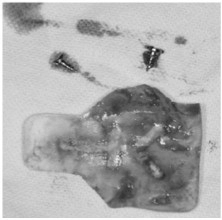

아래턱 잔존 치아 발치 후

한 달 반 정도 지났을 때

충분한 뼈이식을 동반한

임플란트 식립을 진행하였는데요.

상실된 치아의 개수에 맞게

식립을 하면 가장 좋겠지만

처음 내원 당시 잇몸뼈 상태가

많이 좋지 않았었기 때문에

안정적으로 식립이 가능한 위치를 선정하여

식립을 도와드렸으며,

고정형 스크류를 통해

이식한 뼈가 단단히 자리 잡을 수 있도록

고정해 주었습니다.